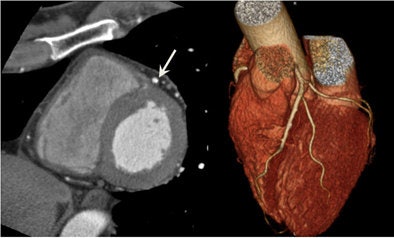

Breath-hold CT and free-breathing CT

Image quality comparison shows no significant differences between breath hold and free-breathing techniques.